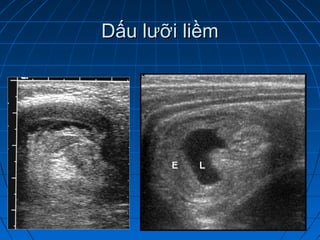

Dấu lưỡi liềm: xuất tiết dịch trong lòngDấu lưỡi liềm: xuất tiết dịch trong lòng

quai ruột ngoàiquai ruột ngoài

Dấu lưỡi liềmDấu lưỡi liềm

Biến chứng củalồng ruộtBiến chứng của lồng ruột ruột non giãn ứ dịchruột non giãn ứ dịch tăng nhu động ruộttăng nhu động ruột thành ruột phù nềthành ruột phù nề tăng hoặc giảm tưới máu thành ruộttăng hoặc giảm tưới máu thành ruột dịch ổ bụngdịch ổ bụng hơi ổ bụnghơi ổ bụng Dấu lưỡi liềm: xuất tiết dịch trong lòngDấu lưỡi liềm: xuất tiết dịch trong lòng quai ruột ngoàiquai ruột ngoài